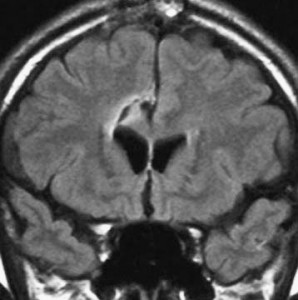

左側頭葉のびまん性星細胞腫です。左側のT1強調ガドリニウム像ではほとんど腫瘍は見えません。真ん中のT2強調画像でも見づらいです。右側のフレア画像で白くにじんでいるところに腫瘍があります。どこまでが腫瘍の境界なのかがはっきりしない腫瘍です。左の海馬(記憶の中枢)を侵し,とてもゆっくり大きくなるタイプで,この患者さんは10年以上治療をしないで経過を見ています。全摘出できない星細胞腫グレード2です。